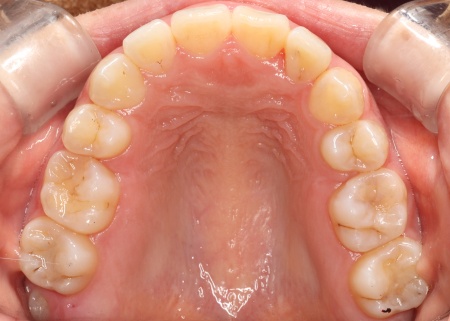

ワイヤー矯正である程度歯並びが整ったら、マウスピース矯正に移行します。

最後に、歯並びと噛み合わせがしっかりと整ったことを確認し、治療を終了しました。

- 年齢・性別 20代女性

- 治療期間の目安 約1年5ヶ月

- 治療回数の目安 16回

- 治療費総額の目安 1,092,300円